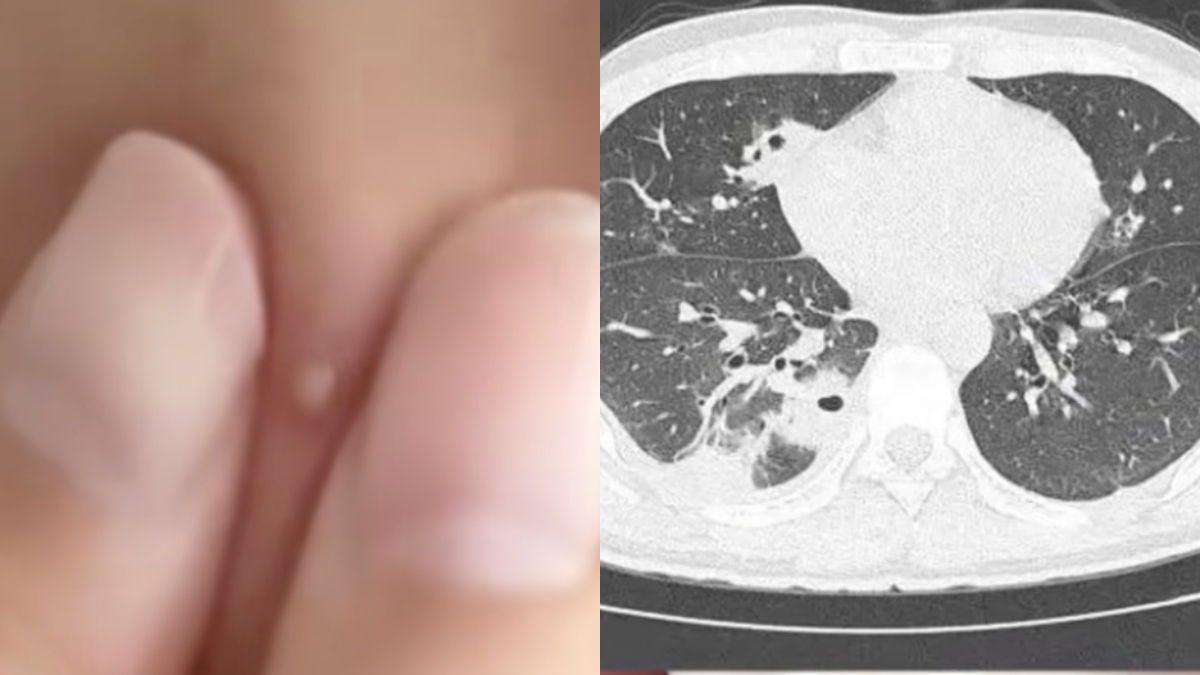

医生检查发现,小林肺部有十多个空洞,而且部分肺组织坏死,是典型的“血源性肺脓肿”,这是一种因细菌感染导致肺部组织坏死并形成充满脓液的空腔。

此外,小林的血液里还检测出金黄色葡萄球菌,这种细菌藏在每个人的皮肤表面。

而且,小林没有洗手,挤痘痘时把细菌挤进血管,引发了败血症,细菌侵蚀到肺部,引发炎症。所幸,小林年轻、身体素质好,经过12天的治疗,最终康复出院。